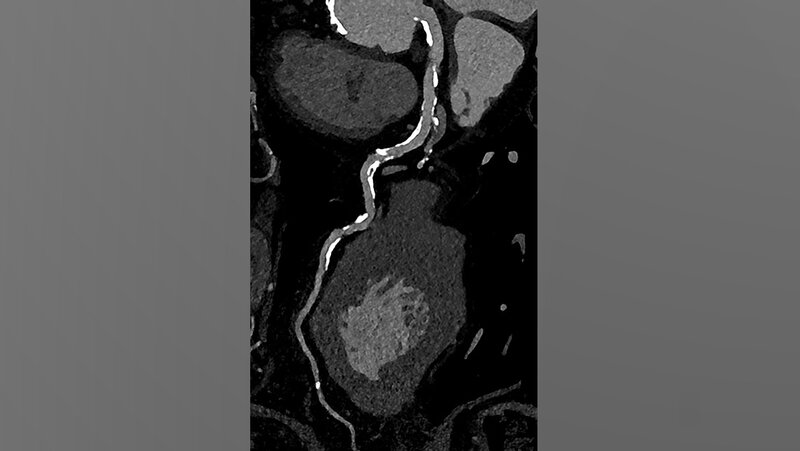

Die koronare CT-Angiographie eignet sich besonders gut zum Ausschluss einer koronaren Herzerkrankung bei Patientinnen und Patienten mit niedrigem oder mittlerem Risiko für Veränderungen der Herzkranzgefäße. Bei Personen mit hohem Risiko gestaltete sich dies bislang aufgrund von häufig auftretenden koronaren Verkalkungen und Stents jedoch schwierig.

Muhammad Taha Hagar, Erstautor der Studie und Arzt der Klinik für Diagnostische und Interventionelle Radiologie am Universitätsklinikum Freiburg erklärt: „In klassischen CT-Bildern erscheinen Verkalkungen der Herzkranzgefäße oft größer als sie tatsächlich sind. Dieser Effekt ist umso stärker, je größer die Verkalkung ist.“ Dadurch konnte es bislang zu einer Überbewertung von Verengungen und Plaques und in der Folge zu einer Überbehandlung kommen. Darum wurden diese Personen bislang schnell in den Herzkatheter überweisen oder in der Magnetresonanztomografie untersucht.

In der von Hagar und seinem Team durchgeführten Studie wurden 68 Probandinnen und Probanden mittels Photon-Counting-CT und einer invasiven Koronarangiografie als Referenzstandard untersucht. Die Patientinnen und Patienten litten alle unter einer schweren Aortenklappenstenose, einer gängigen, aber ernsthaften Herzerkrankung, die den Blutfluss vom Herzen zur Aorta reduziert oder blockiert. Die Photon-Counting-CT-Untersuchung zeigte sich sehr genau in der Erkennung oder dem Ausschluss der koronaren Herzerkrankung. Auch wurde die Bildqualität in fast 80 Prozent als gut oder hervorragend bewertet.